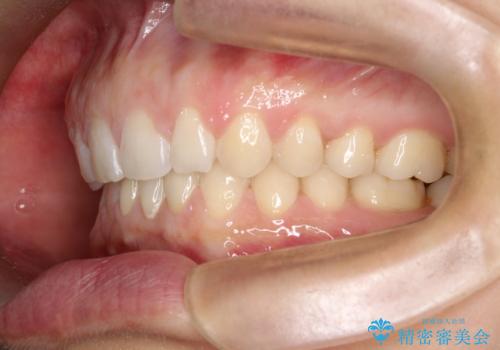

【空隙歯列】ワイヤー矯正で短期間に治療を終えたい

- 歯と歯の間に隙間があることを主訴に来院されました。

短期間での治療終了を希望され、ワイヤー矯正にて治療を行い1年ほどで治療を終了しております。

下顎前歯は矯正後補綴治療を行なっております。

期間や仕上がりで大変満足していただきました。